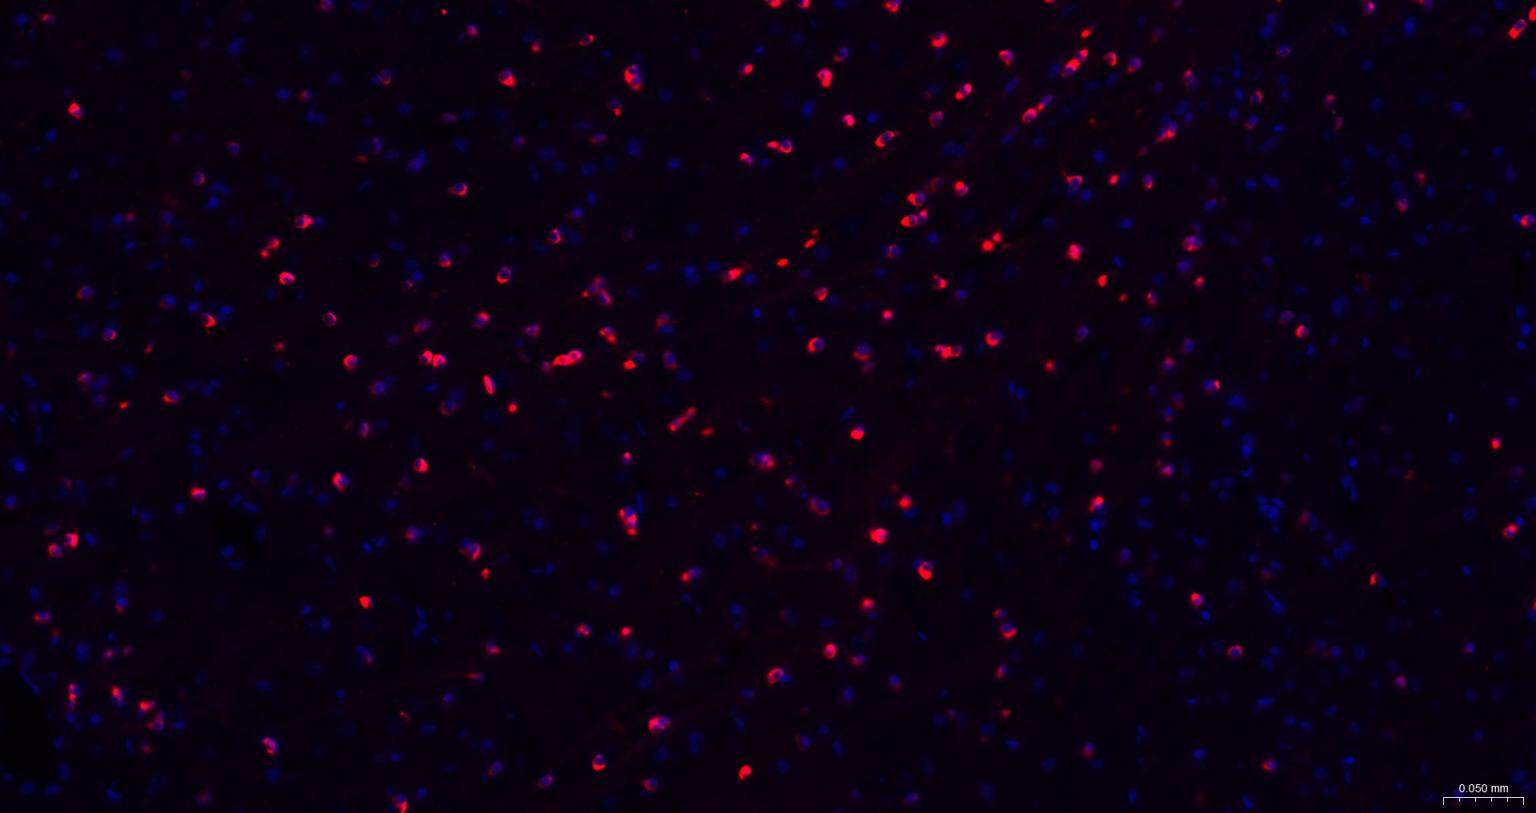

Paraformaldehyde-fixed, paraffin embedded Mouse Cerebrum; Antigen retrieval by boiling in sodium citrate buffer (pH6.0) for 15 min; The section was incubated with NMDAR1 Monoclonal Antibody, Unconjugated (bsm-52950R) at 1:200 overnight at 4°C. Followed by conjugated Goat Anti-Rabbit IgG antibody (Red, bs-0295G-BF594), DAPI (blue, C02-04002) was used to stain the cell nuclei.